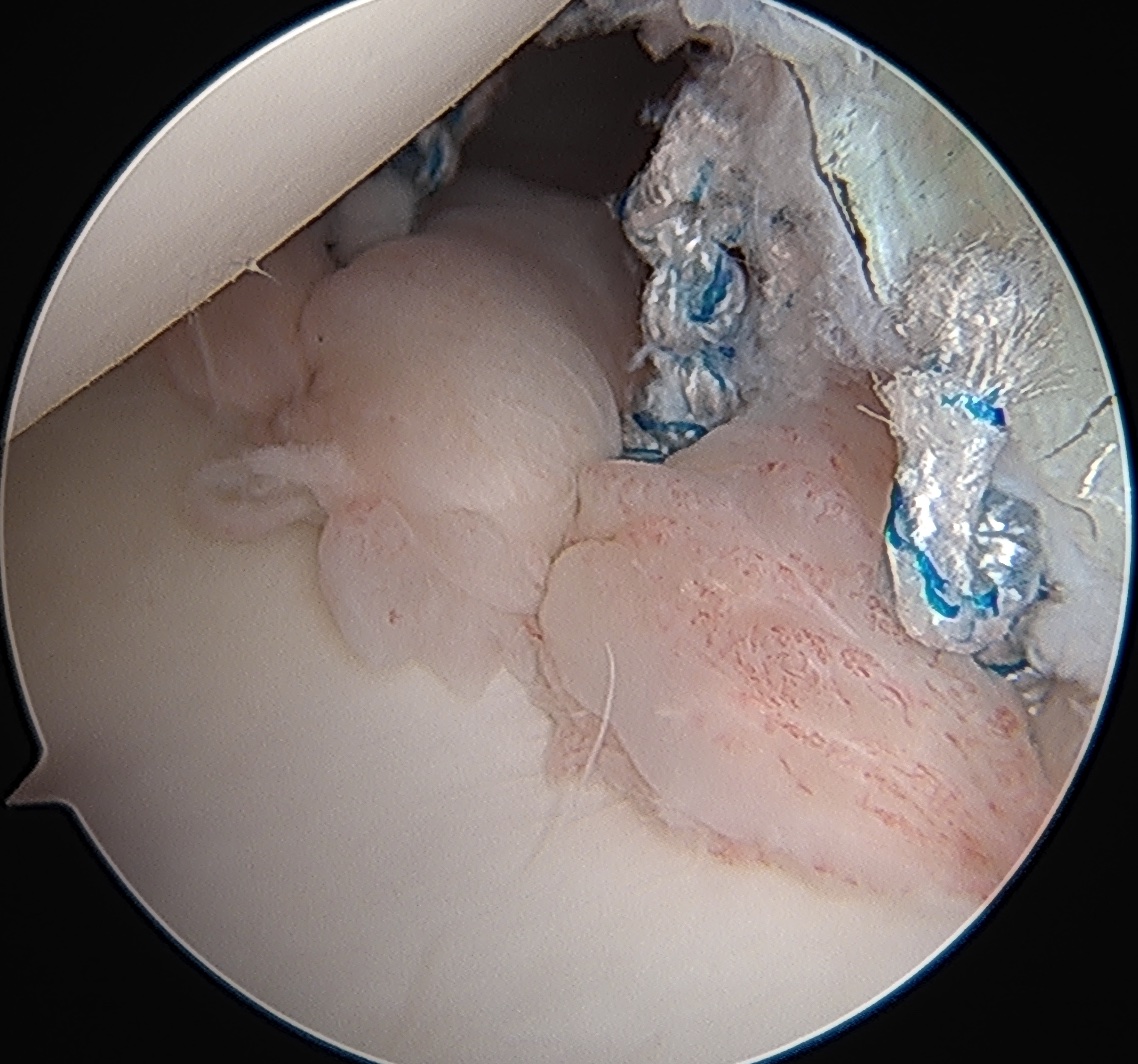

Posterior labral tear

Posterior labral tear

Kim lesion

- Kim lesion

- incomplete and concealed avulsion of the posteroinferior labrum

- superficial portion attached, deep portion detached

- labrum flat with loss of normal height resulting in retroversion of the chondrolabral glenoid

Posterior labral repair